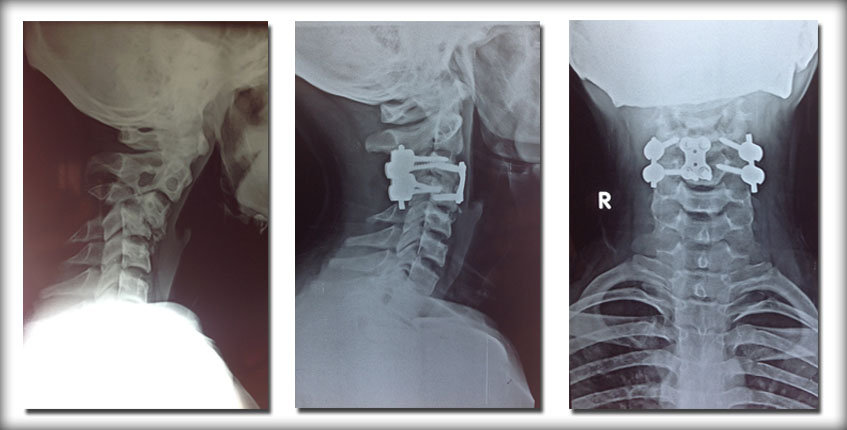

ODONTOID FRACTURE:

58yr old male with hepatic dysfunction presented with inability to walk due to odontoid fracture and atlanto axial dislocation (1yr old injury) leading to cord compression. Dislocation was reduced and stabilized with C1-C2 screw fixation. Patient had neurological recovery and was able to walk in 6 weeks’ time.

Case Example: